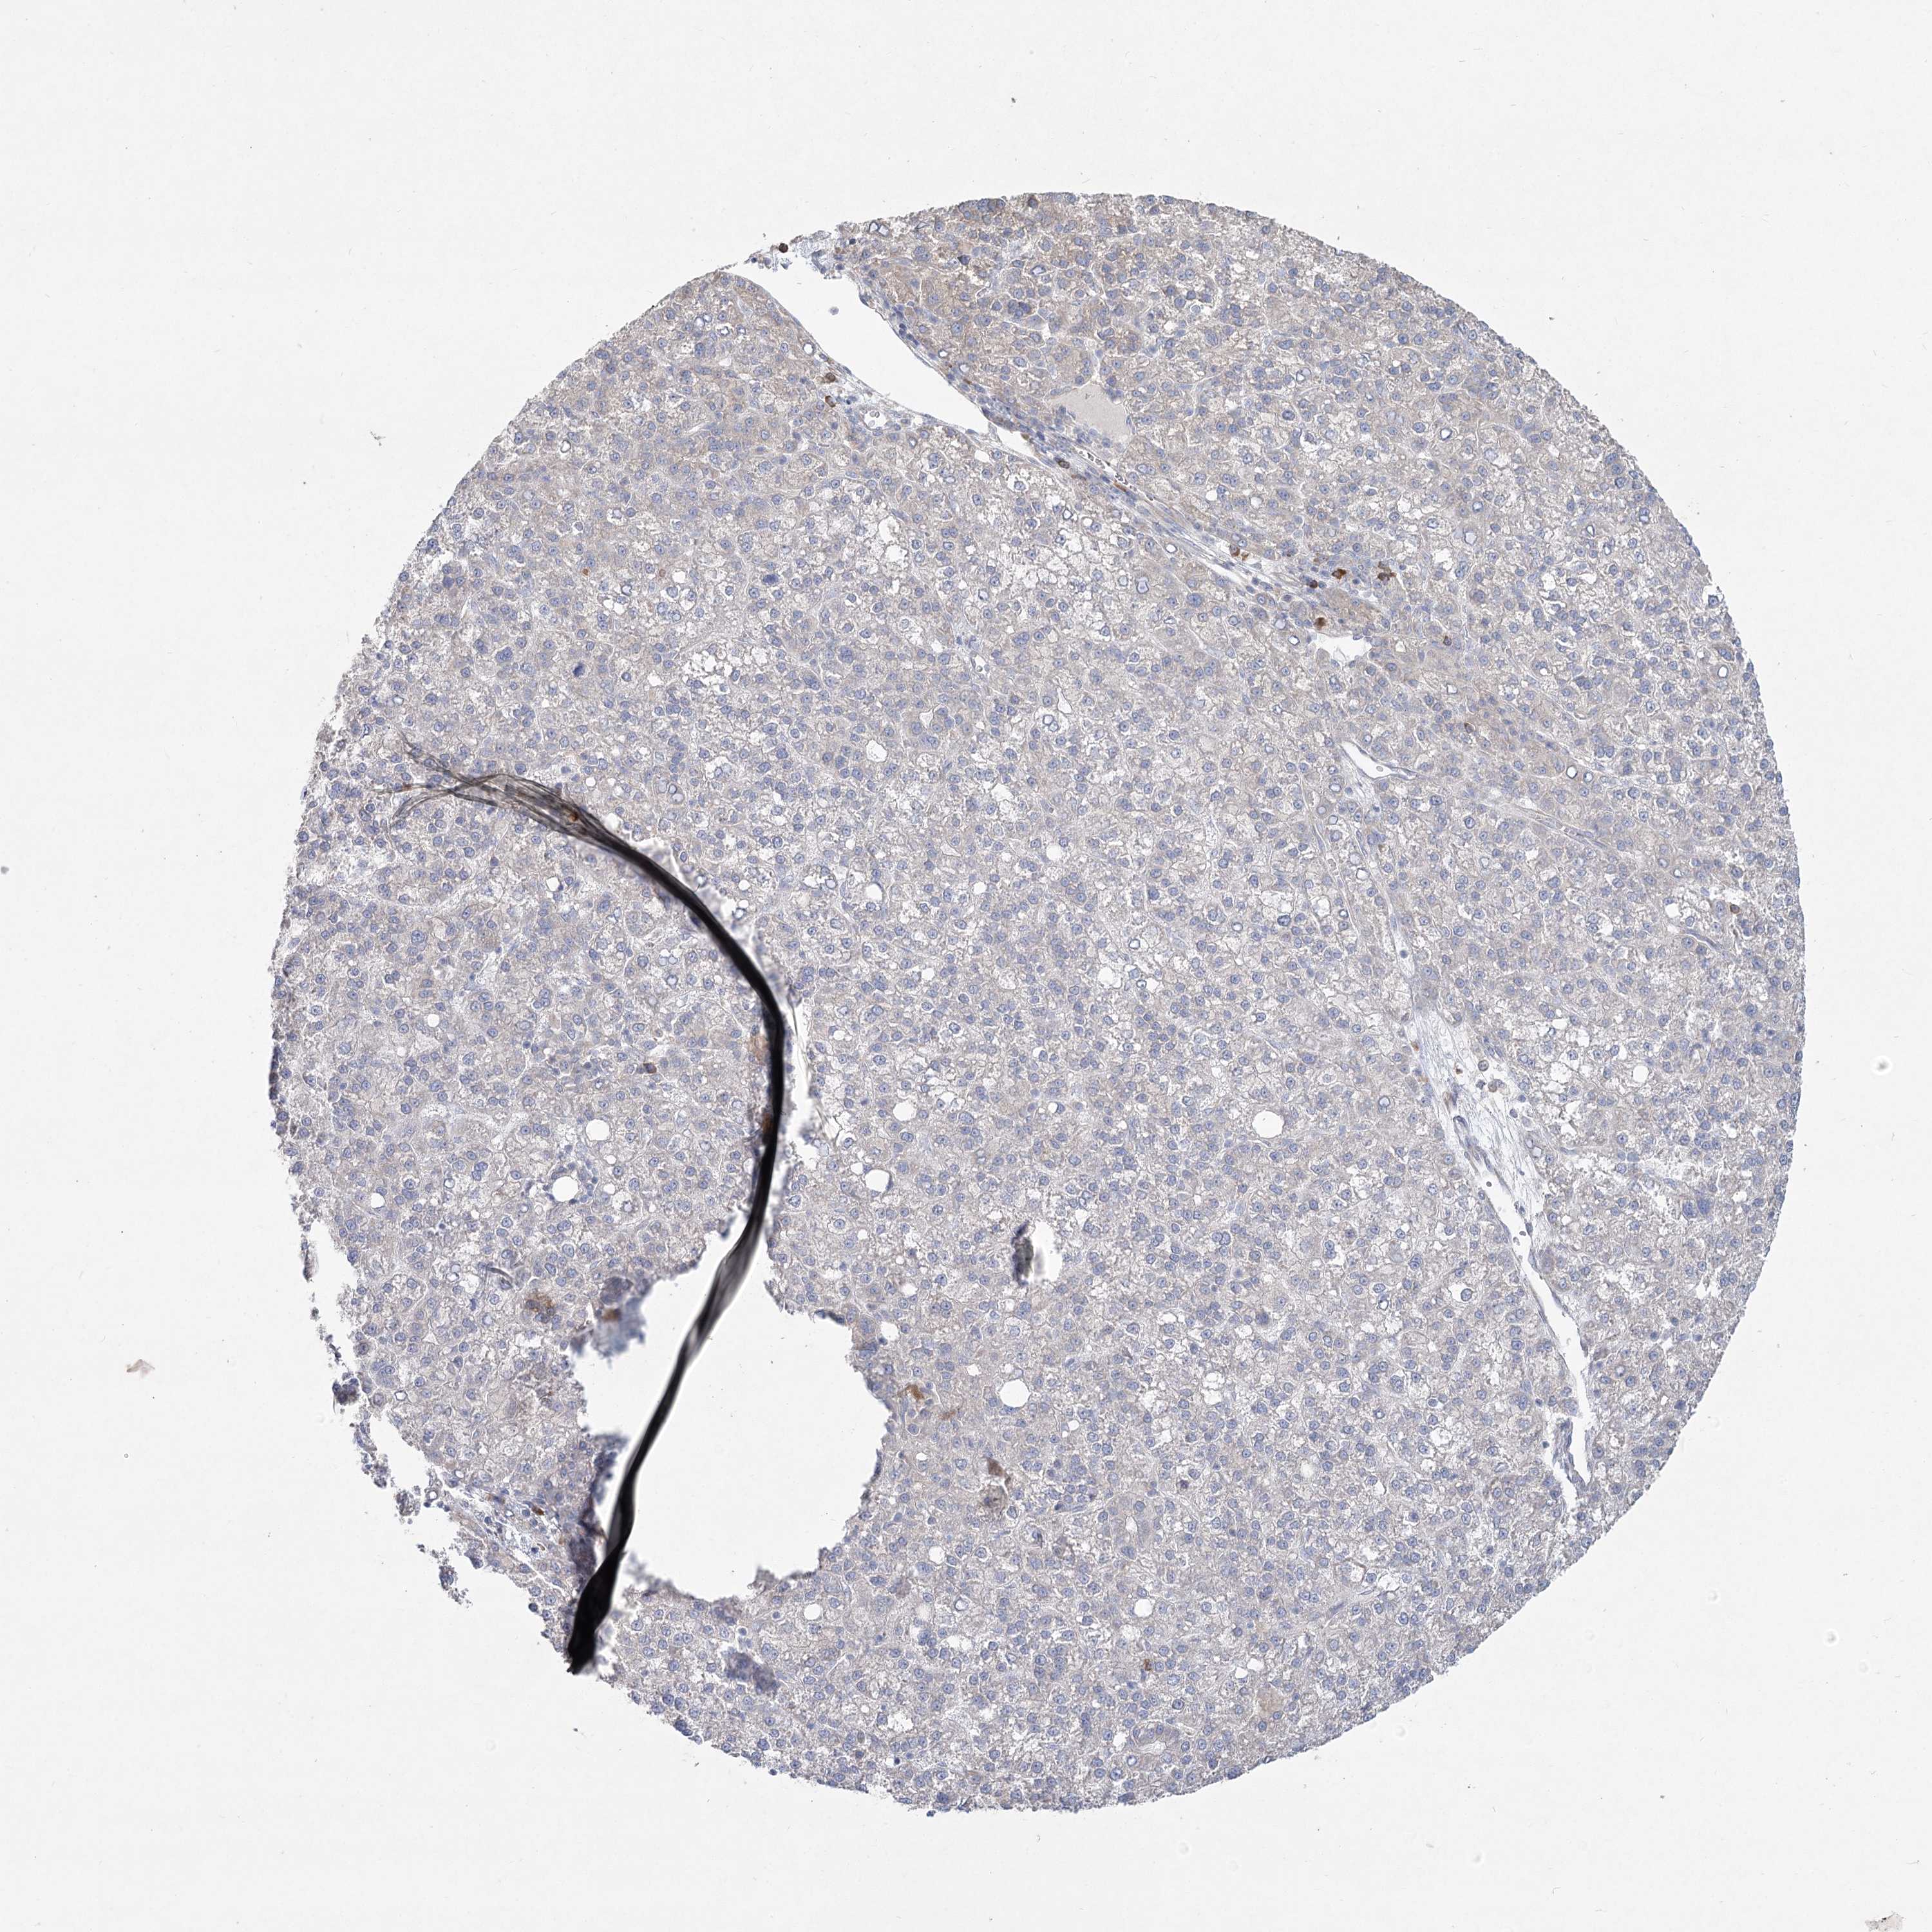

LIVER CANCER - Protein expressioni

A mouse-over function shows sample information and annotation data. Click on an image to view it in a full screen mode. Samples can be filtered based on level of antibody staining by selecting one or several of the following categories: high, medium, low and not detected. The assay and annotation is described here.

Note that samples used for immunohistochemistry by the Human Protein Atlas do not correspond to samples in the TCGA dataset.

Antibody stainingi

Antibody staining in the annotated cell types in the current human tissue is reported as not detected, low, medium, or high, based on conventional immunohistochemistry profiling in selected tissues. This score is based on the combination of the staining intensity and fraction of stained cells.

Each image is clickable and will lead to virtual microscopy that enables deeper exploration of all samples and also displays staining intensity scores, fraction scores and subcellular localization as well as patient and tissue information for each sample.

Antibody HPA036342

Antibody HPA036343

Staining

High

Medium

Low

Not detected

Intensity

Strong

Moderate

Weak

Negative

Quantity

>75%

75%-25%

<25%

None

Location

Nuclear

Cytoplasmic/membranous

Cytoplasmic/membranous,nuclear

Cholangiocarcinoma

Carcinoma, Hepatocellular, NOS